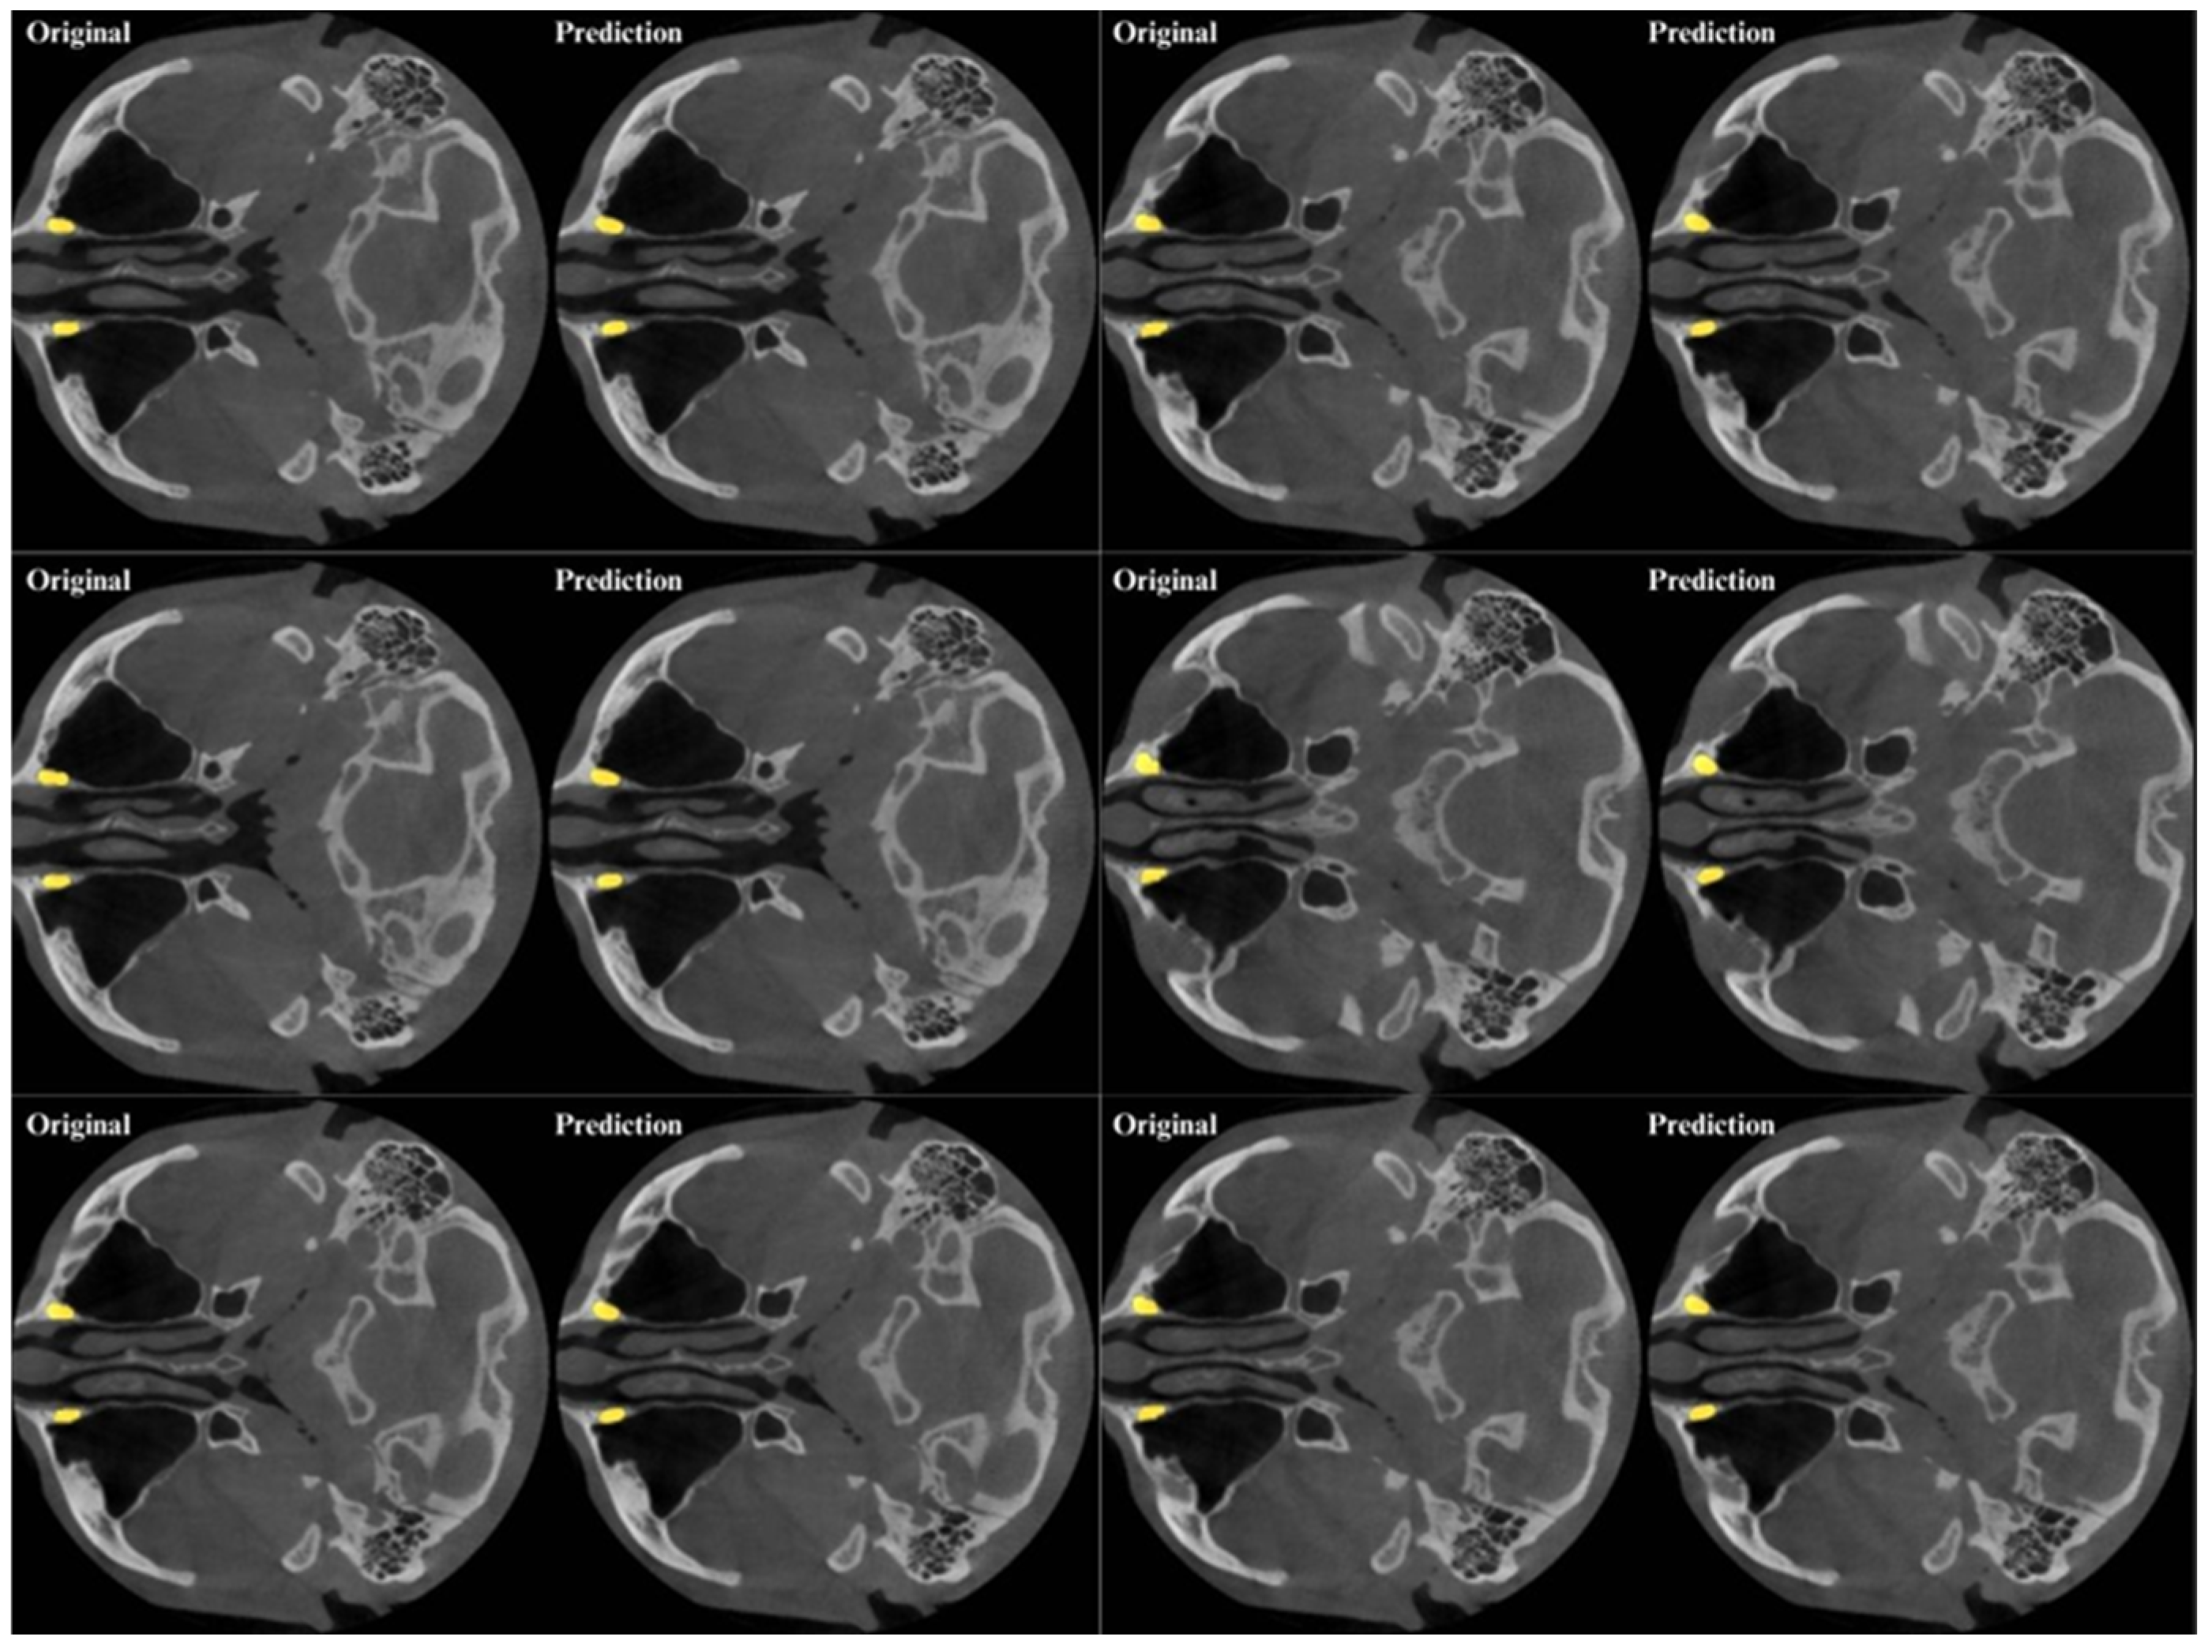

3. Results